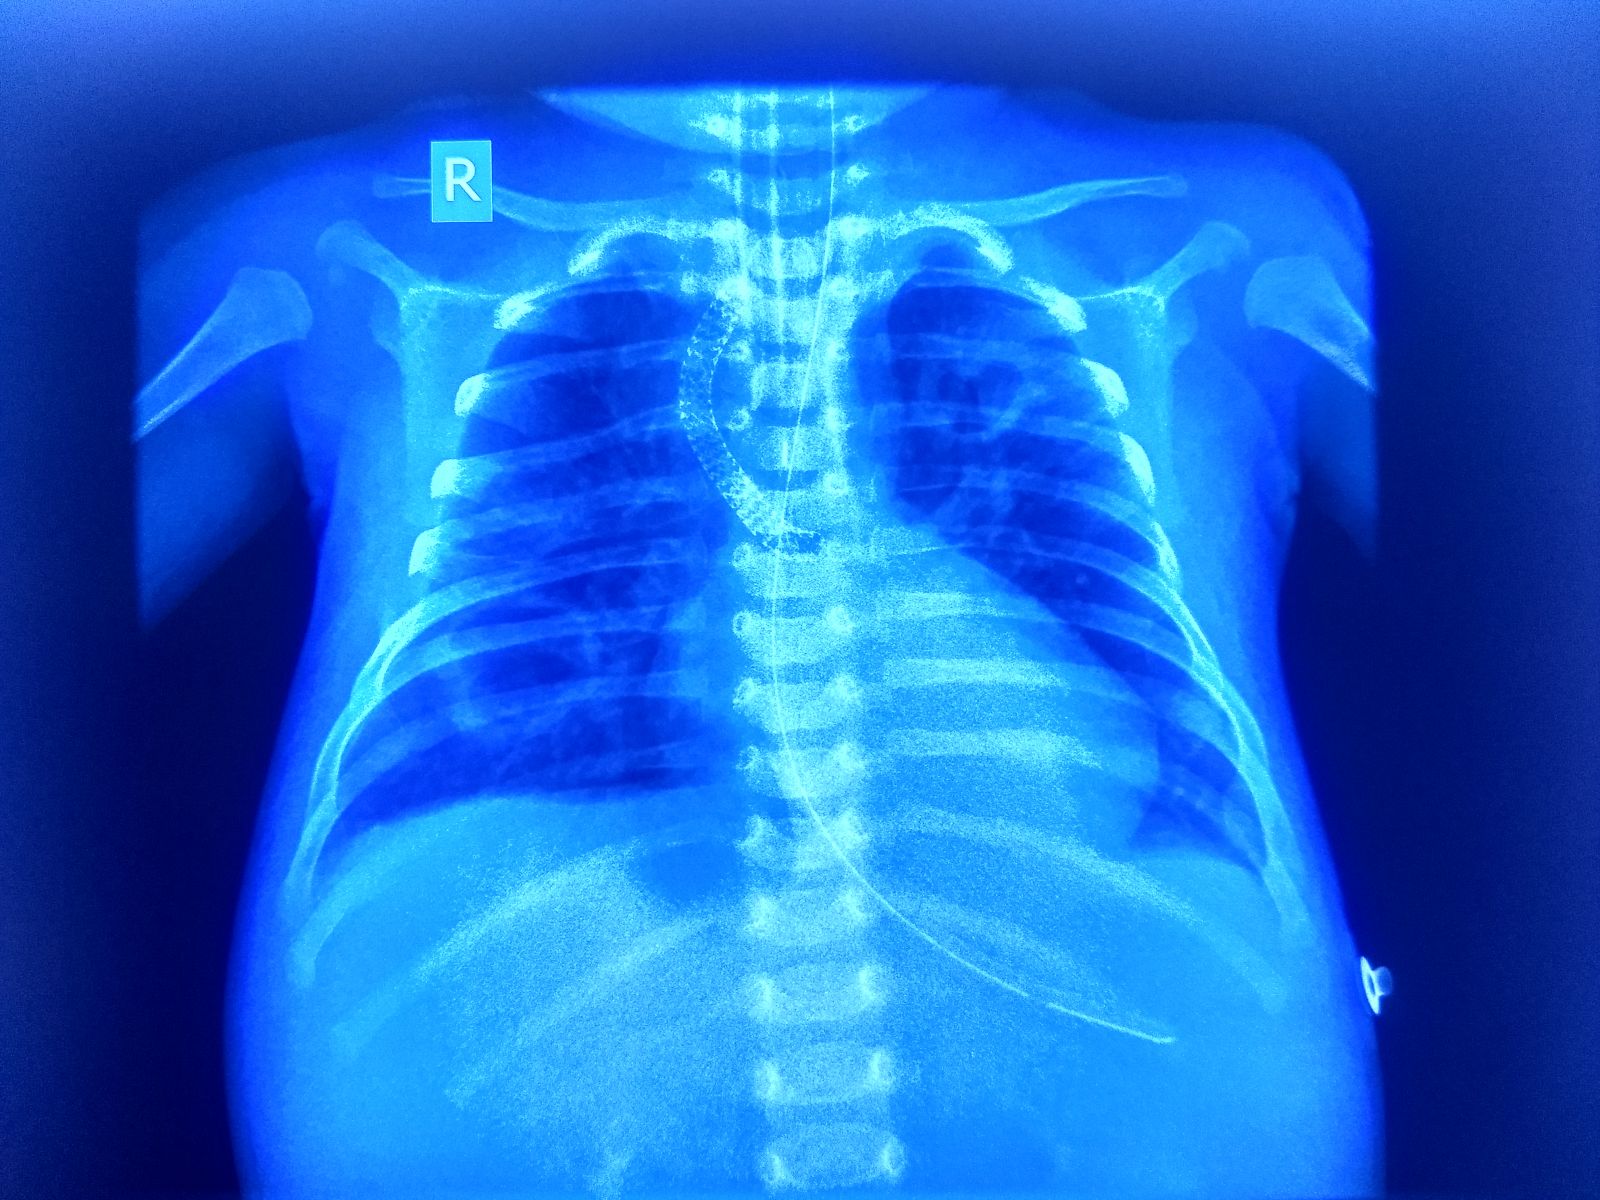

A 3-month old male child presented to ER with respiratory distress, fever and poor feeding. Child was a known case of Tetrology of Fallot and palliative surgery in form of Right modified Blaclok- Taussig shunt was performed at day 3 of life. At time of presentation Child was hypotensive with HR -200/bpm, RR-80 breath /min, BP-50/30 and his SPO2 was 50 % on room air which improved to 55 % on high flow oxygen therapy. In view of hemodynamic instability and impending respiratory failure child was intubated and started on ventilator support. After giving fluid boluses @ 20 ml/kg, inj nor- adrenaline was started in view persisting hypotensive shock. However, in spite of all above measure child’s blood pressure remained less than 5th centile for age and his saturation remained below 60%. ECHO done showed absent flow in shunt. Child was taken for emergency Cath and stenting of the B-T shunt was done. Post procedure child hemodynamic improved, His SpO2 improved to 80% , inotropes were tapered and stopped. Child was subsequently extubated after 40 hrs.